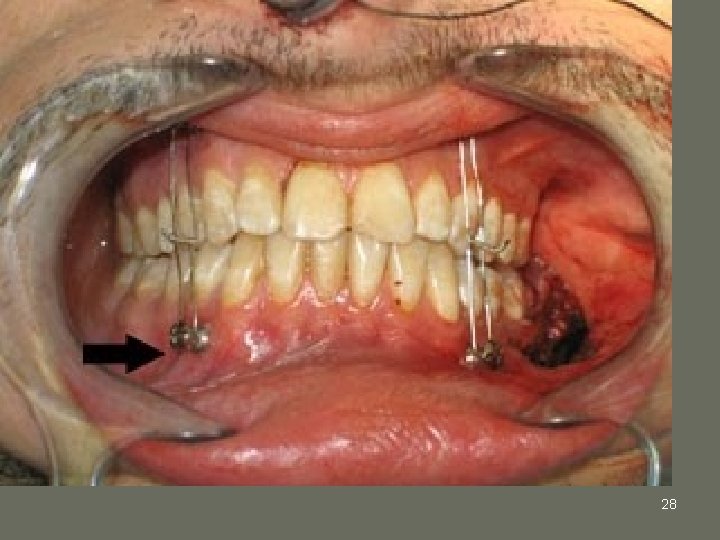

28